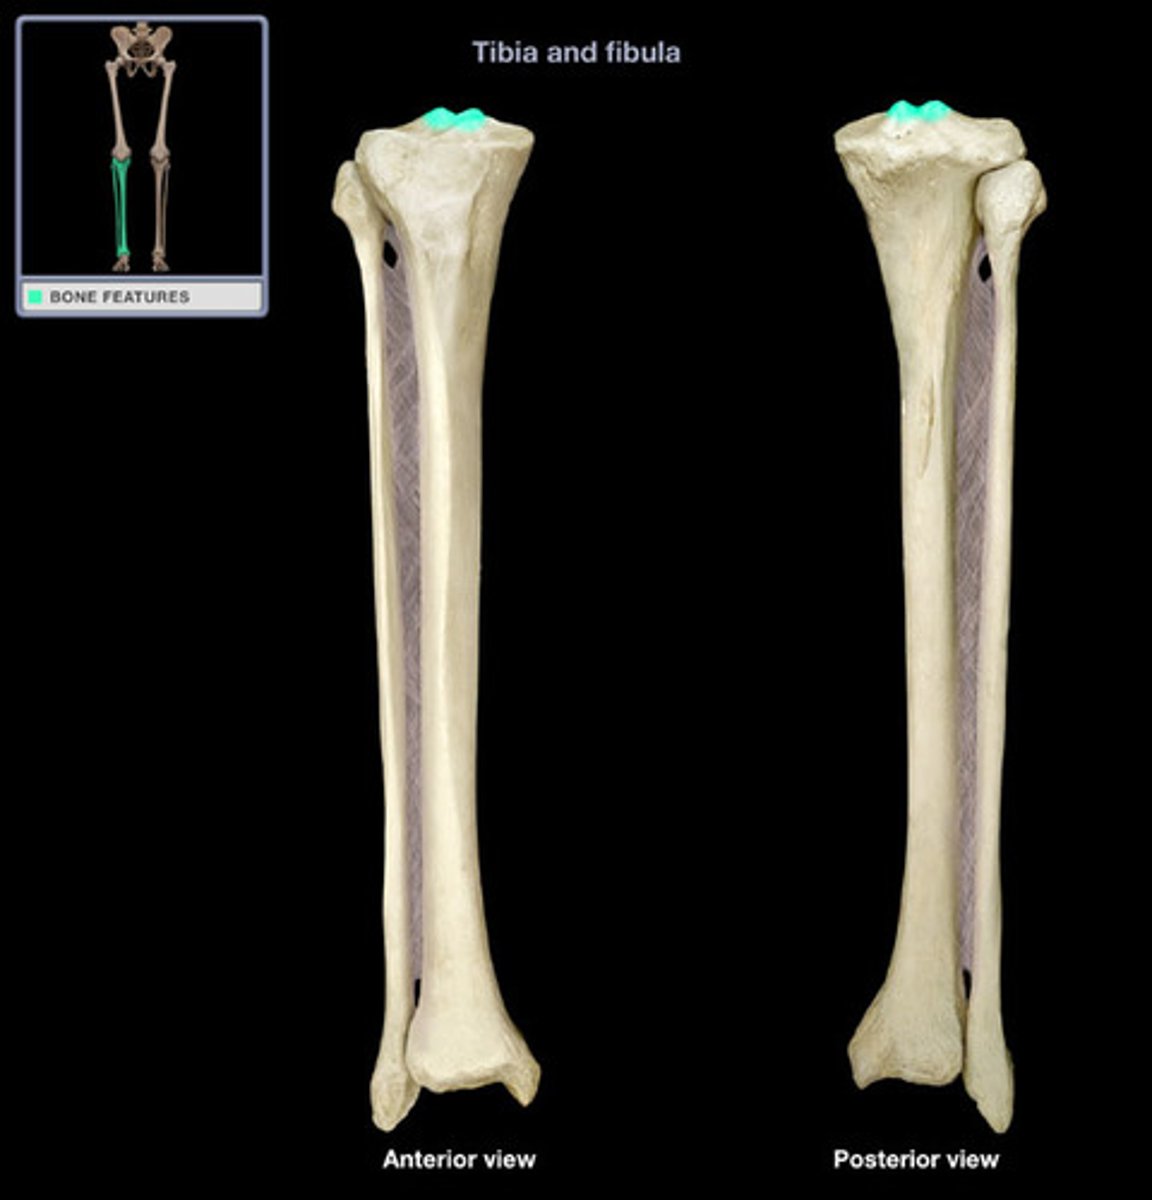

Intercondylar eminence

Anterior intercondylar area

A

Posterior intercondylar area